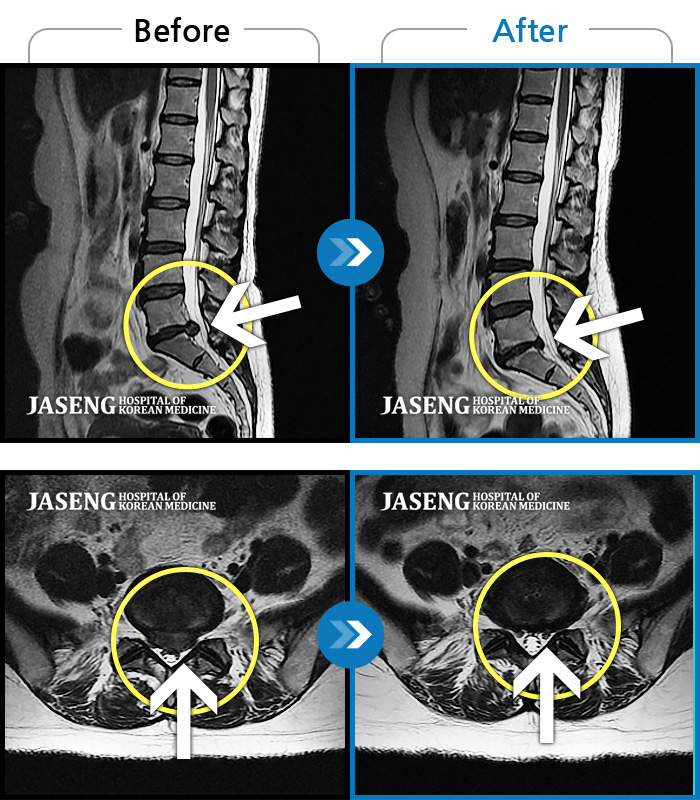

허리 골반 통증이 있고 다리가 저리고 아파 걷기가 힘들다.

2025.02.10 ~ 2025.09.13